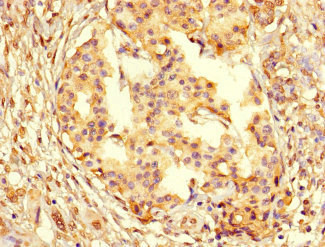

Immunohistochemistry of paraffin-embedded human pancreatic cancer using CSB-PA01567A0Rb at dilution of 1:100